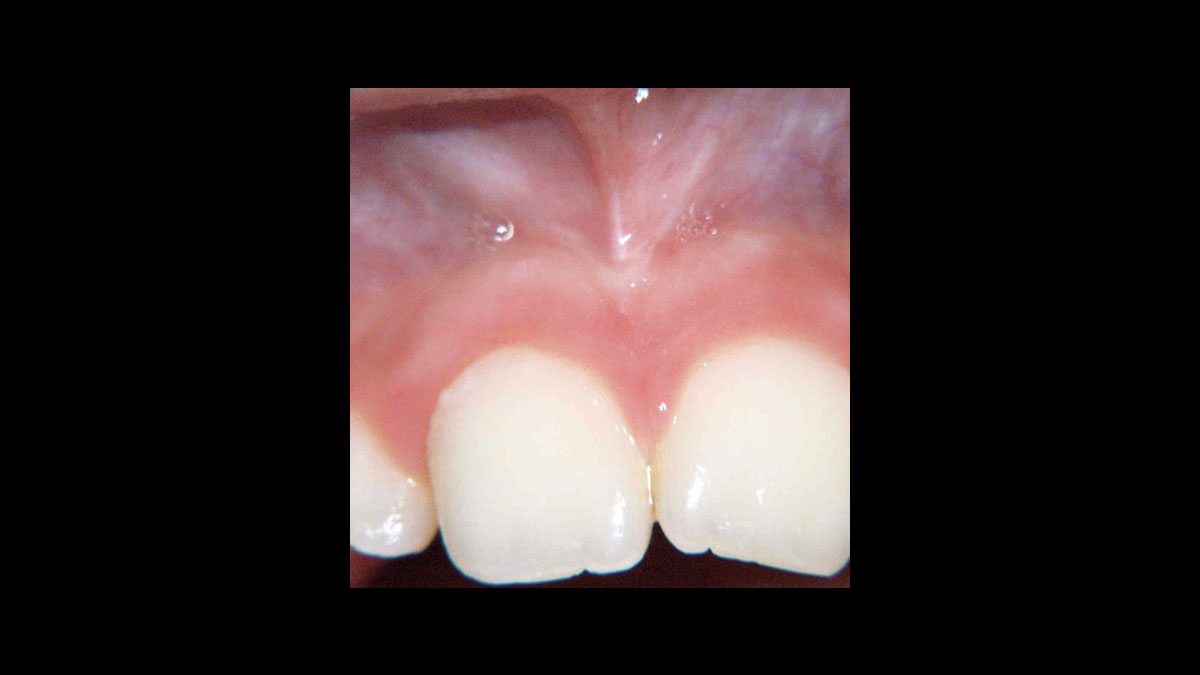

• Frenectomía

Frenectomía